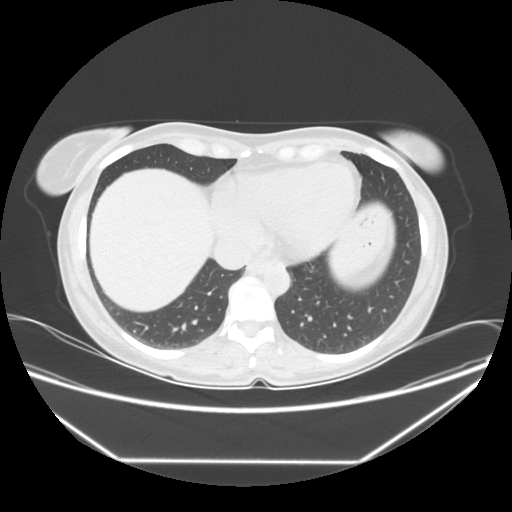

Original VENOUS CT scan

Lung window (WL -600, WW 1500 β†’ Low βˆ’1350, High +150)